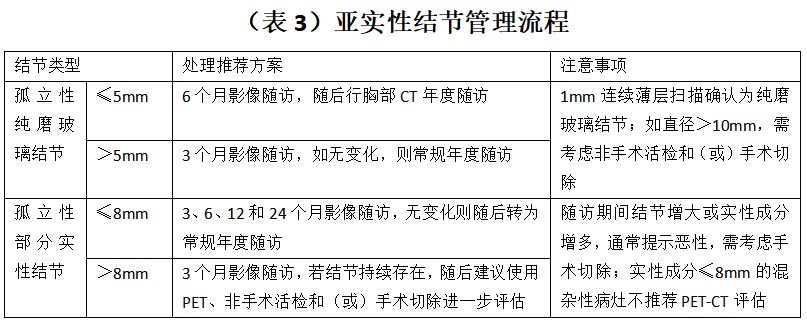

总结临床上,尽管肺结节的评估手段是多元化的,包括病史、影像学检查、肿瘤标志物检查、功能显像以及一些有创检查和手术,但临床上医生最可及的是病史、胸部 CT,部分医院可完成肿瘤标志物检查,费用在几百元不等,有一定参考价值。但对于 PET-CT,因其费用较高,作为常规评估比较困难。有创的评估检查手段主要是针对前面几种方式综合评估为高危的患者所采取的方法,临床普及性不强。因此,肺部结节究竟是手术还是随访,如何进行随访重点在于病史和胸部 CT,综合评估肺结节恶性概率、结节大小、密度、是单发还是多发等多种因素,制定个体化治疗及随访方案。